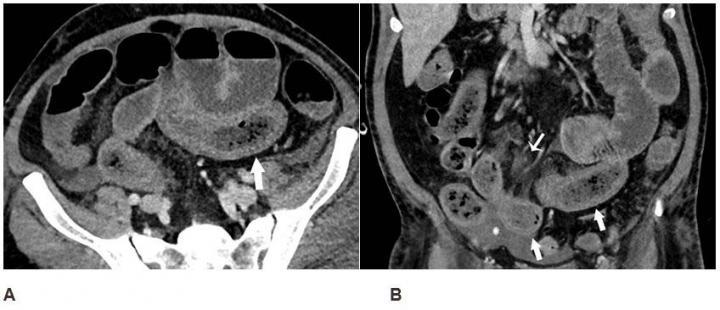

Abdominal Trauma Imaging Intechopen